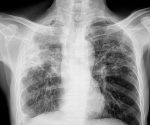

Health experts have claimed the next pandemic could easily dwarf the death toll caused by COVID-19 as scientists prepare for ‘Disease X’.